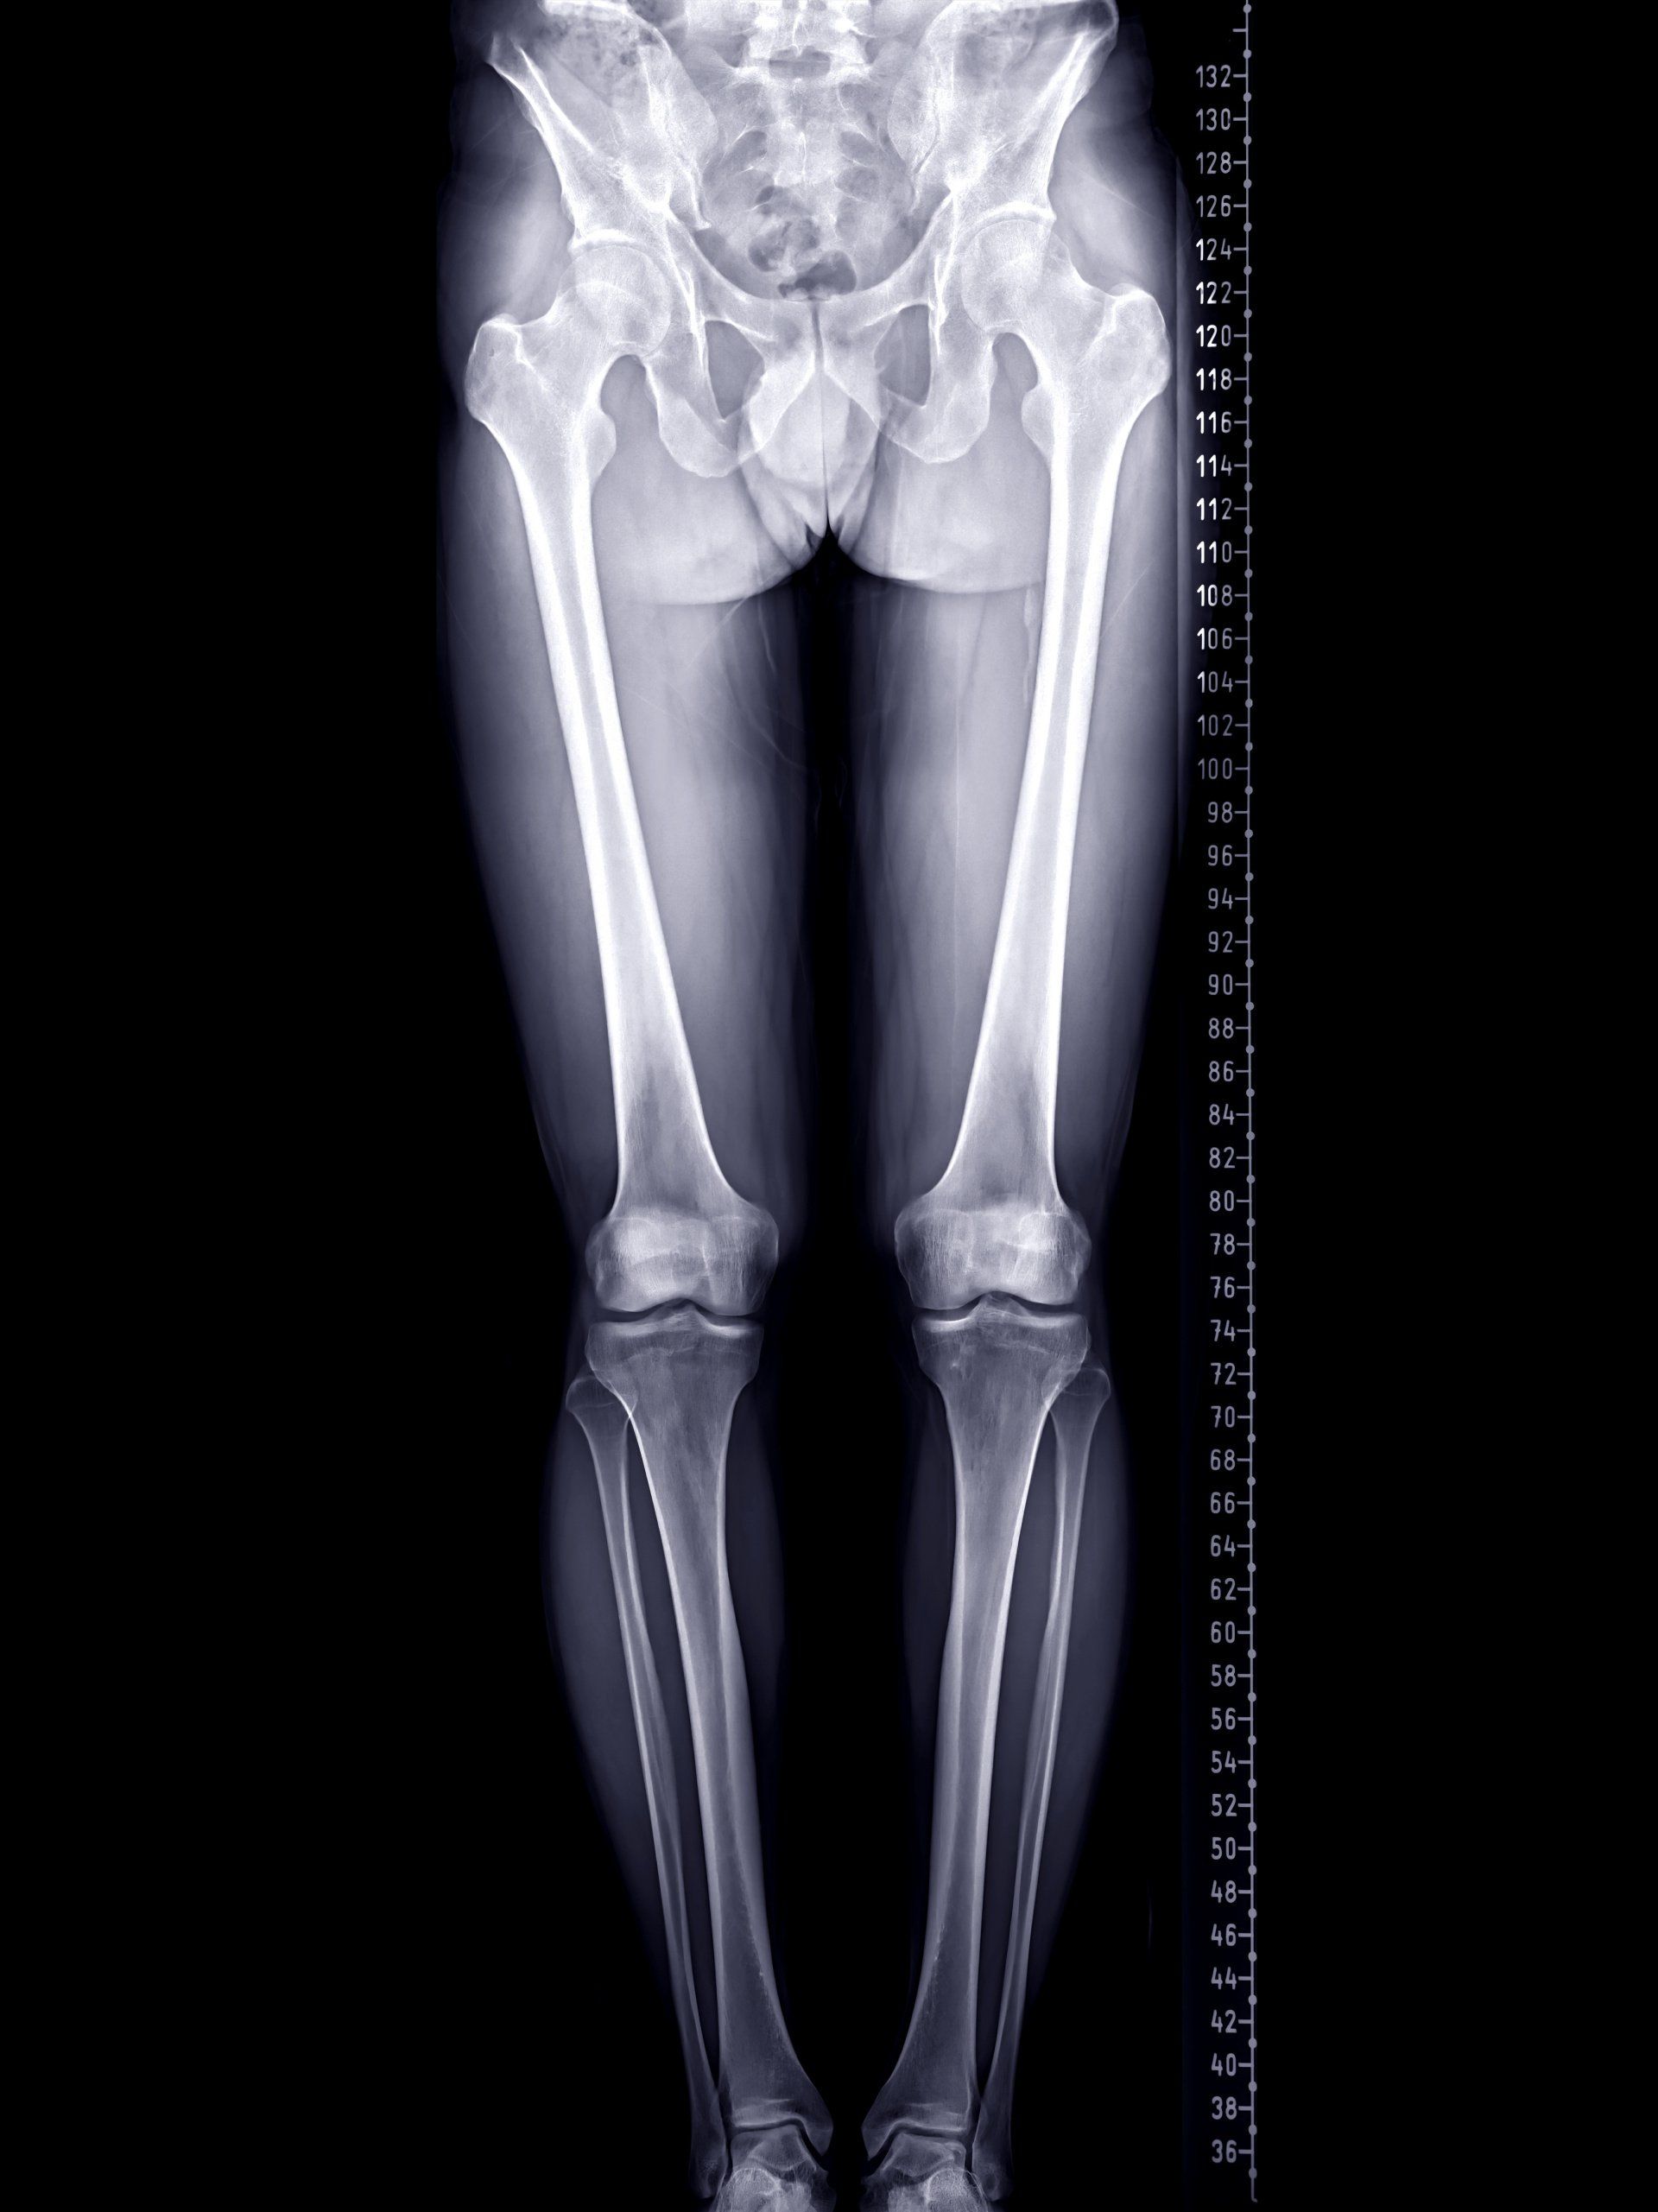

- Ακτινογραφίες ευθυγράμμισης όλου του κάτω άκρου:

- Ακτινογραφίες και των δύο κάτω άκρων σε όρθια θέση από τη λεκάνη ως την ποδοκνημική

- Από τις ακτινογραφίες ευθυγράμμισης όλου του κάτω άκρου, ο ορθοπαιδικός θα μπορεί να υπολογίσει τη θέση και τον βαθμό παραμόρφωσης και τον απαιτούμενο βαθμό διόρθωσης

- Αυτό θα βοηθήσει στη συνέχεια να προσδιοριστεί:

- Πού να πραγματοποιηθεί οστεοτομία (κνήμη ή μηρός)

- Ποιος τύπος οστεοτομίας θα εφαρμοστεί (ανοιχτής ή κλειστής σφήνας)